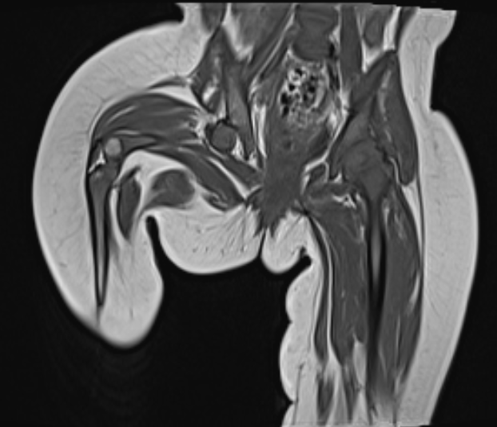

A 13 year old female with complaints of recurrent swelling with on and off pain in left cheek for 7 years, 5-6 episodes/year. Pain on chewing also present.

A 13 year old female with complaints of recurrent swelling with on and off pain in left cheek for 7 years, 5-6 episodes/year.Pain on chewing also present.